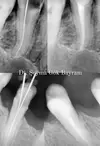

Implant Treatment